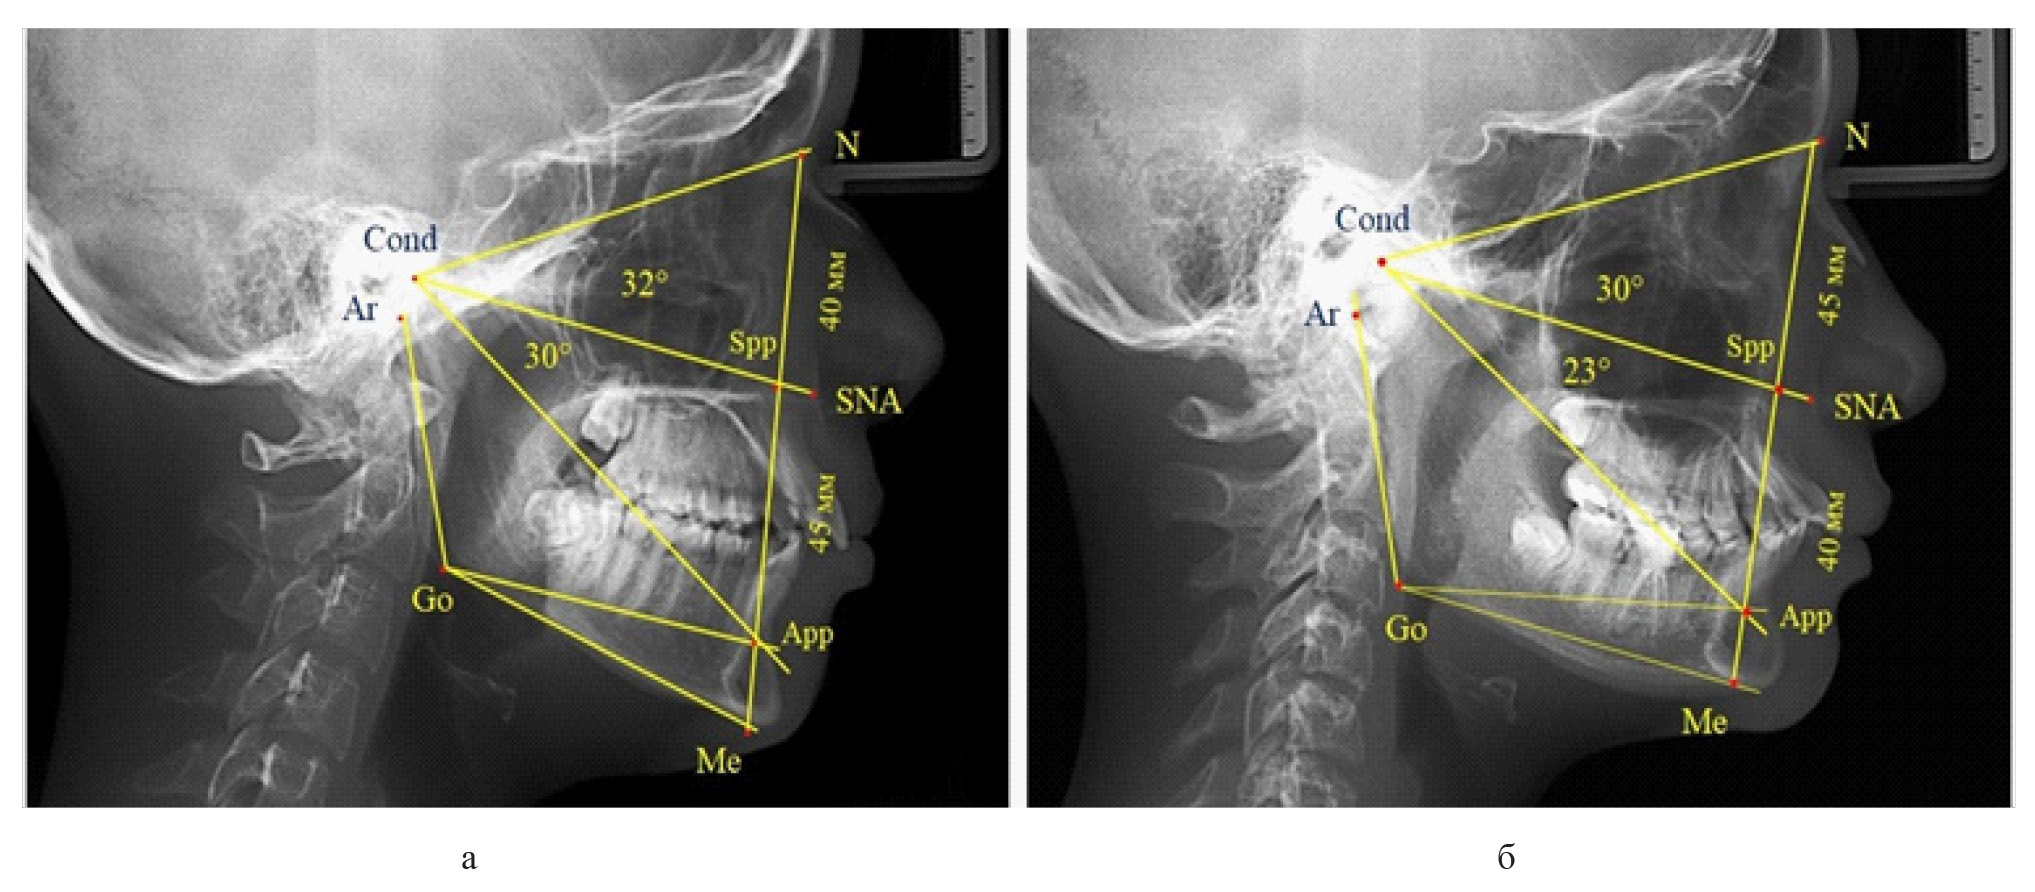

Среди пациентов с аномалиями челюстно-лицевой области в вертикальном направлении у 24 человек определялась глубокая резцовая окклюзия/дизокклюзия (рис. 5).

Рис. 5. Варианты ТРГ с оптимальными размерами носового отдела и оптимальными (а) и укороченными (б) размерами гнатической части лица

При этом только в двух случаях [(8,33 ± 5,64) %], параметры носового и гнатического отдела соответствовали норме. У 9 человек [(37,59 ± 9,88) %], при оптимальных параметрах назального отдела отмечалось уменьшение высоты гнатического отдела, вплоть до патологических показателей.

У людей с глубокой резцовой окклюзией нередко отмечалось изменение параметров носового отдела лица. Так, в 7 случаях было выявлено снижение параметров как носового, так и гнатического отделов лица. У 5 человек [(20,83 ± 8,28) %], отмечалось уменьшение носового отдела лица при оптимальных параметрах гнатического отдела.

В одном случае [(4,17 ± 4,08) %], определялось патологическое увеличение назального отдела лица при уменьшении гнатической его части. Некоторые варианты ТРГ пациентов с глубокой резцовой окклюзией представлены на рис. 6.

Рис. 6. Варианты ТРГ с уменьшенными размерами носового отдела и оптимальными (а) и укороченными (б) размерами гнатической части лица при глубокой резцовой окклюзии